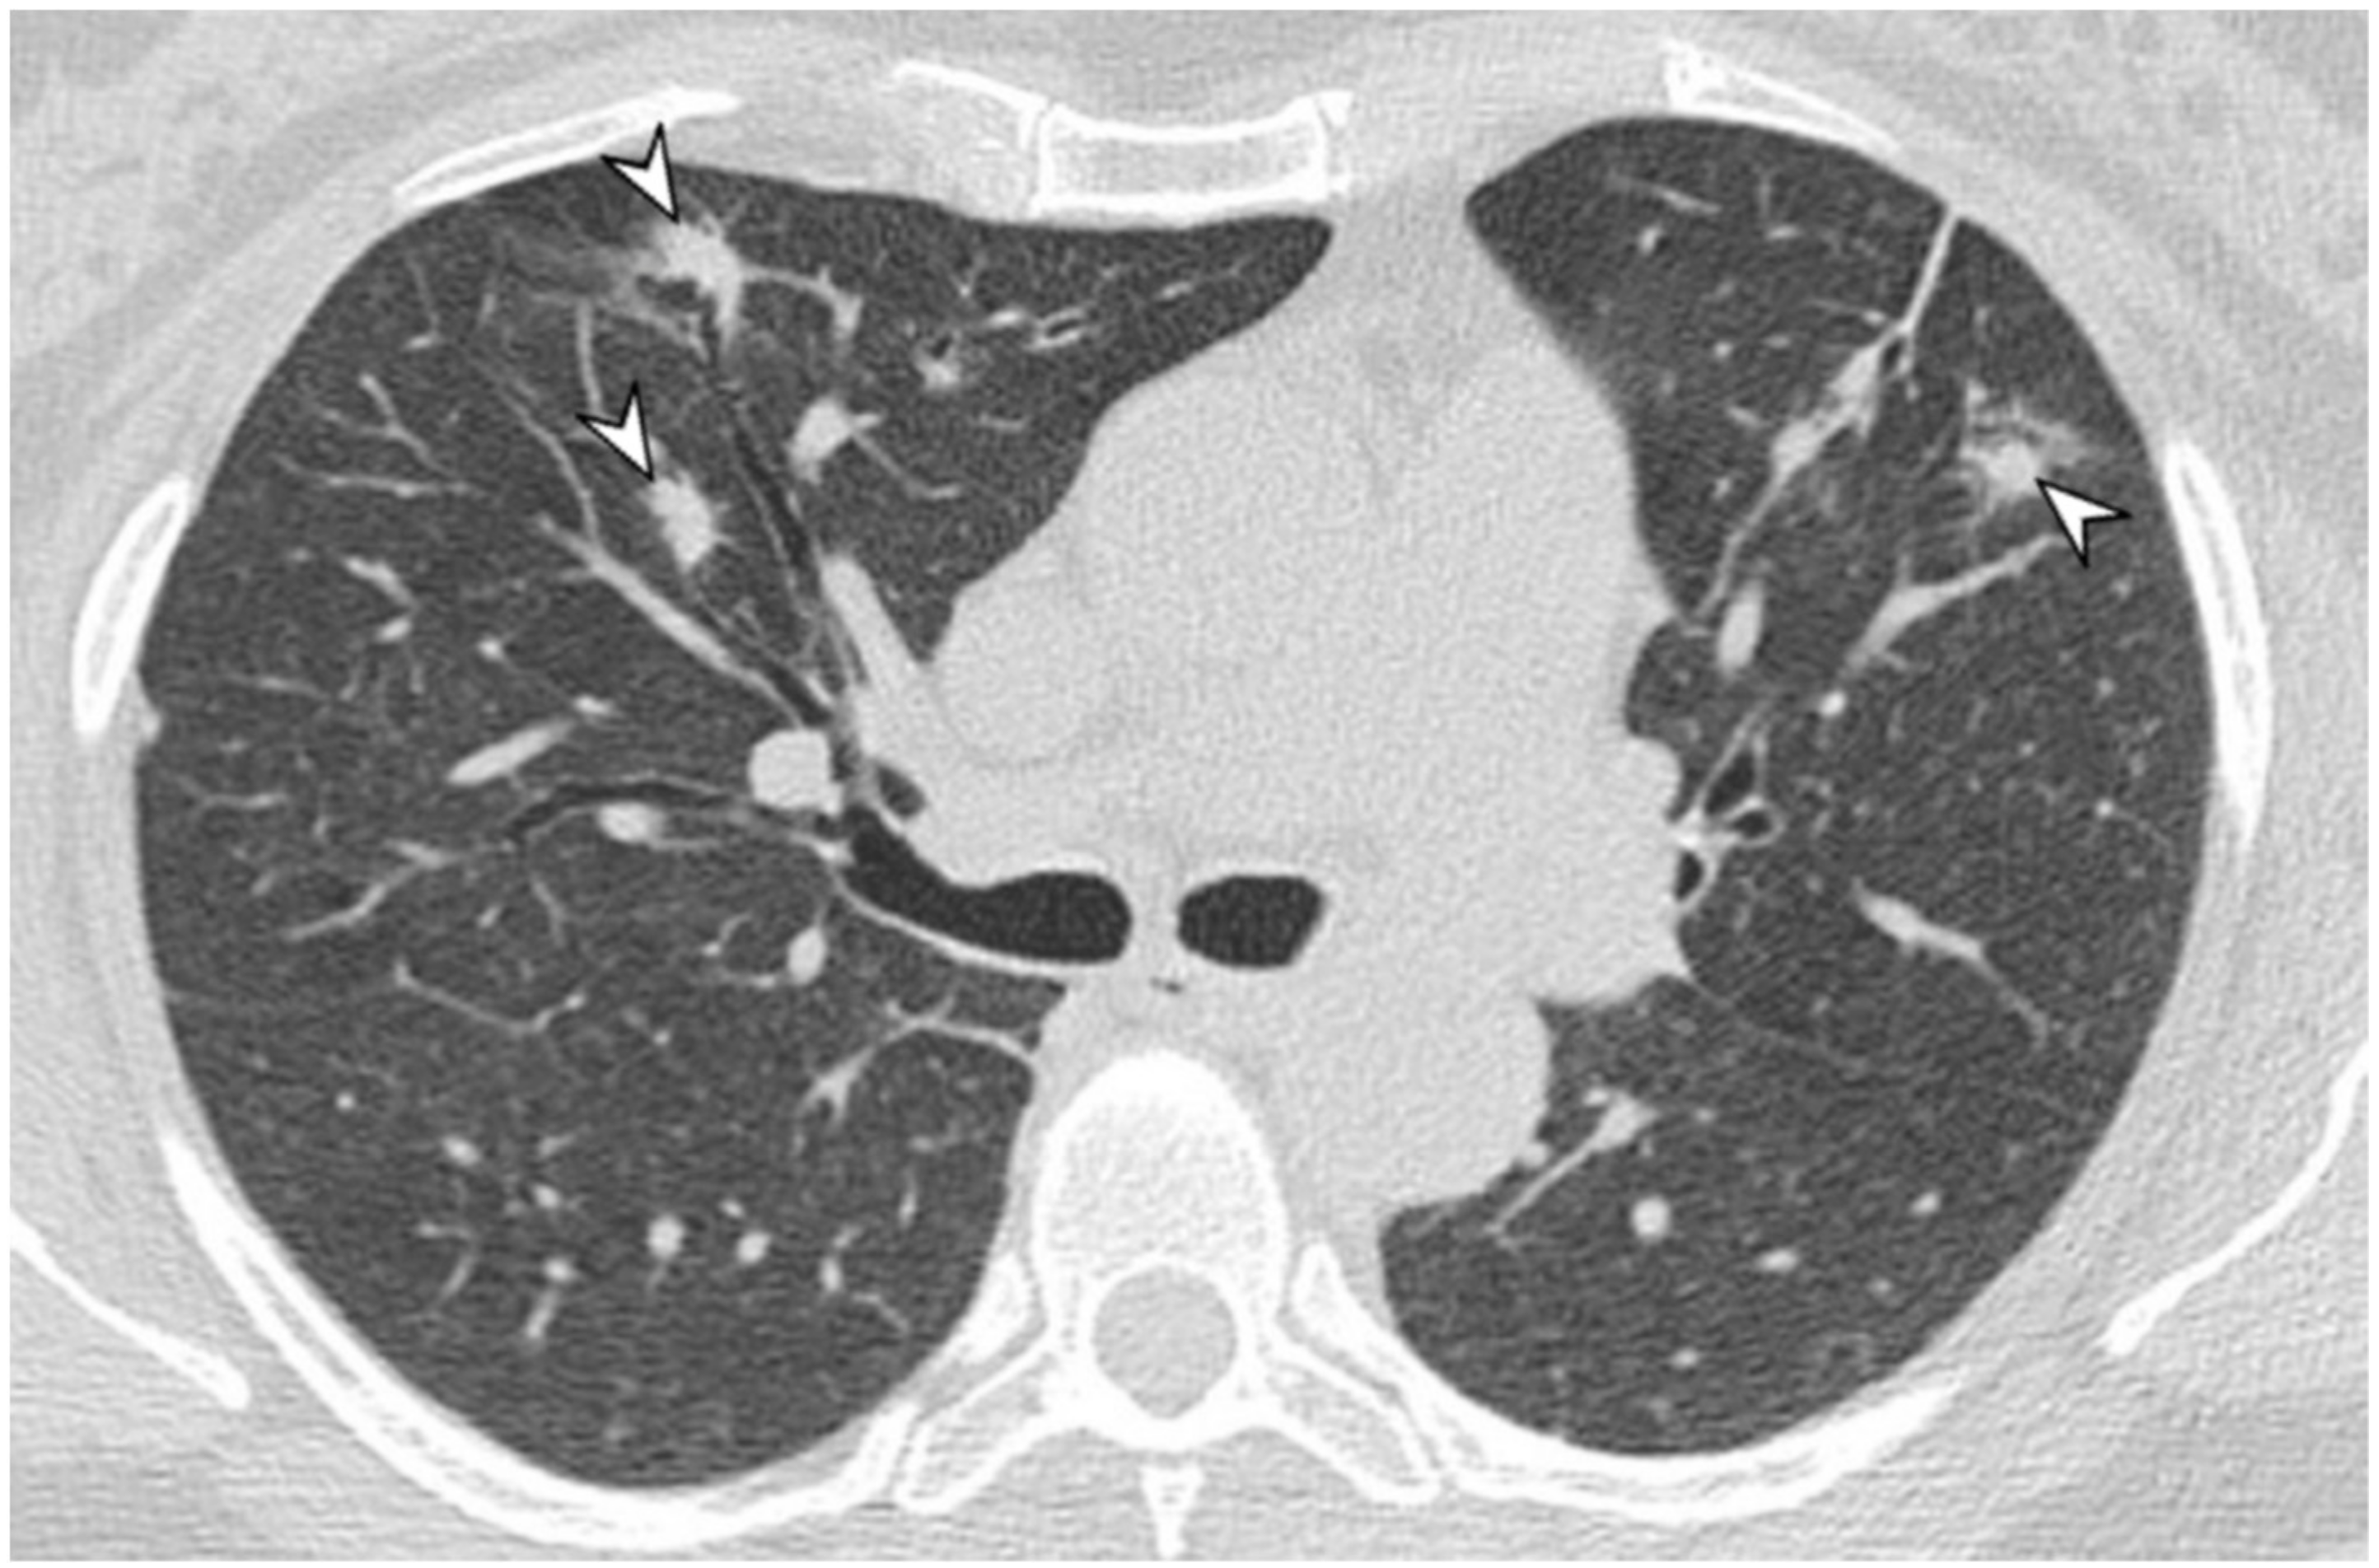

2.5. Eosinophilic Granulomatosis with Polyangiitis (EGPA-Churg-Strauss)

| EGPA | Migrant GGOs, transient consolidation, irregular bronchial wall thickening, small nodules with peribronchial and centrilobular distribution, pleural effusion. |